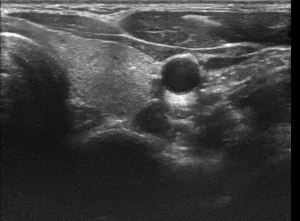

상기환자 외부건진이상소견 세침검사위해 내원하신 30대 중반 여성분으로

의심스러운 갑상선 좌엽 결절 세포검사 진행후 갑상선암으로 진단되었습니다